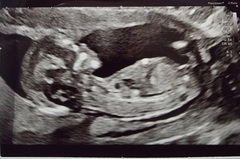

Hi All Does any one have experience with the Nub Theory? I have posted my scans on FB Groups and also paid £10 to the nub Techs. All say boy so I'm guessing I'm having another little boy. But is it accurate? Can I assume I am having a baby boy from this or is it just a total guess? I've already bought a few blue cardigans as the accuracy rate on the website etc is super high! Lol. The baby does have a super "boy" nub from other photos I've seen. Anyone used them and they have been correct or incorrect for you?? Thanks!